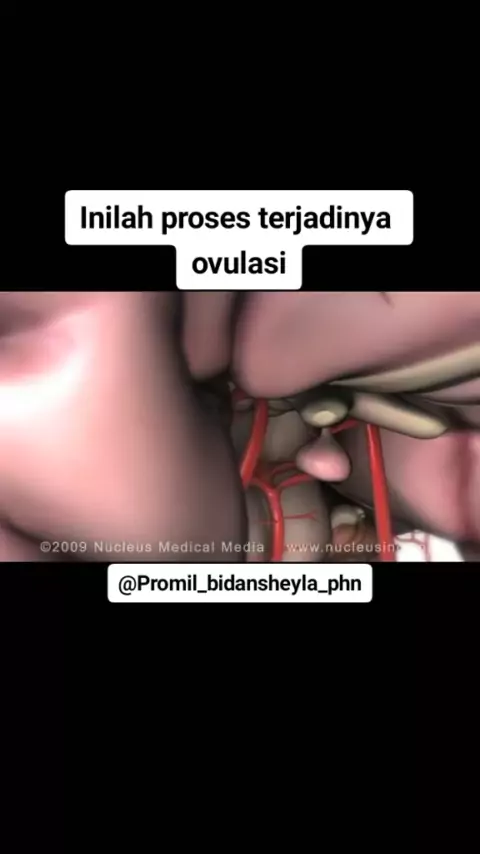

Simak ya bunda, konsul seputar kehamilan bisa lgsg klik bio diatas#melahirkan #ovulasi #promilcepathamil #pejuanggarisdua #dongggggggg #edukasikesehatan

simak ya bunda, konsultasi bisa lgsg via wa bunda#melahirkan #promilcepathamil #pejuanggarisdua #dongggggggg #edukasikesehatan #MAKUKUBestGiftOfLove